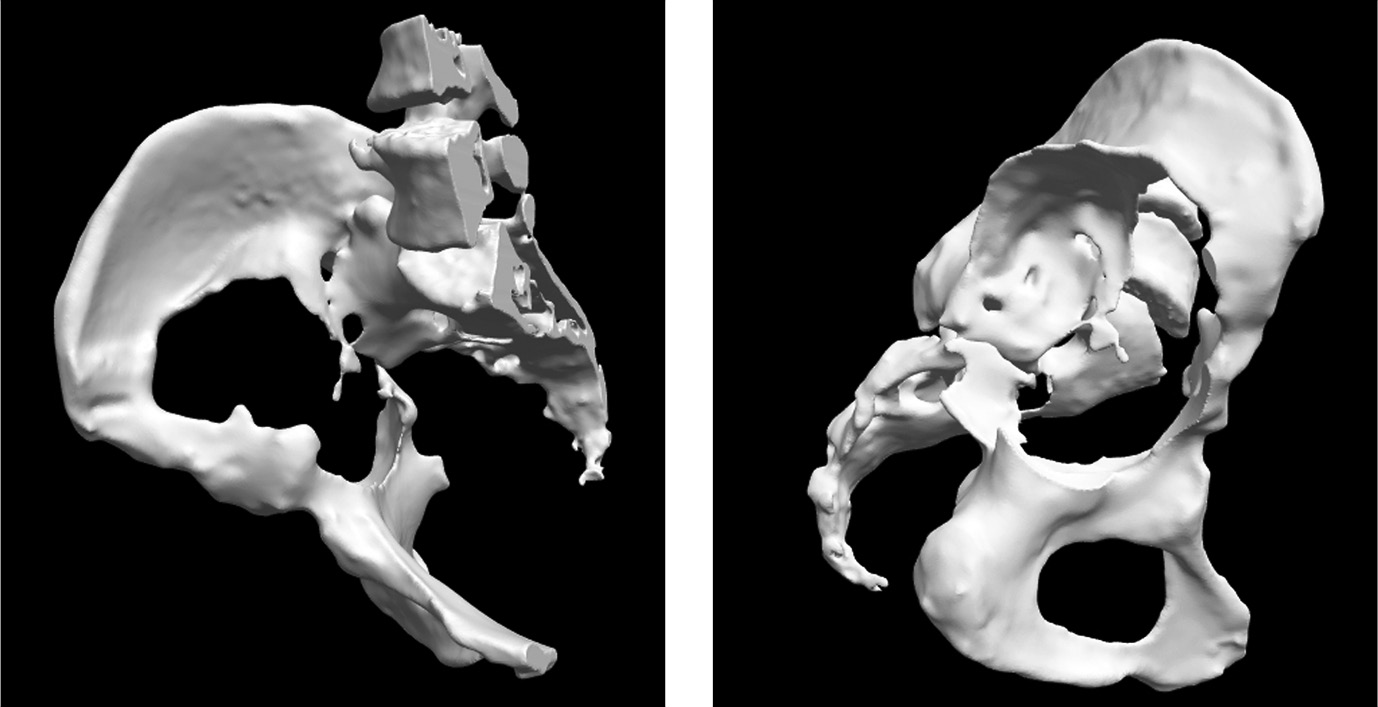

Данные КТ были загружены в программу PMEPLanner. Инженером фирмы POLYGONMED, которые профессионально занимаются 3D-модели-рованием и печатью, произведен процесс сегментации, очищения от наводок и мягких тканей и создание цифровой 3D-модели пораженной стороны таза (рис. 10, 11).

Рис. 10. Компьютерно Т-изображение пораженной части таза после обработки и очищения от наводок, мягких тканей

Рис. 11. Вид модели таза с разных сторон. Визуализация дефектов вертлужной впадины с точностью до 1 мм